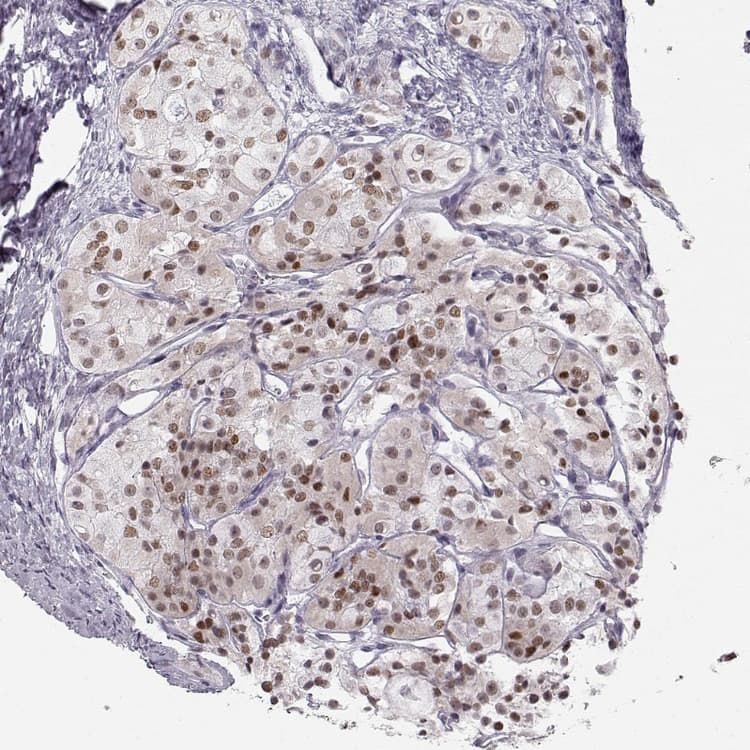

Anti-Homeobox protein SIX6 antibody(ab251658)

Rabbit Polyclonal Homeobox protein SIX6 antibody. Suitable for IHC-P, WB, ICC/IF and reacts with Human samples. Immunogen corresponding to Recombinant Fragment Protein within Human SIX6 aa 50 to C-terminus.

Applications ICC/IF, IHC-P, WB

Species Reactivity Human